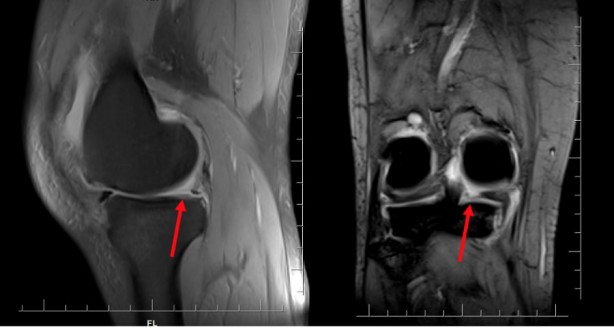

Özellikle sporcularda ve yaşlı bireylerde görülen menisküs yırtığı konusunda bilgi veren Ortopedi ve Travmatoloji Uzmanı Op. Dr. Halil İbrahim Gümüş; "Menisküs yırtığı, dizde en sık meydana gelen ağrılı ve zayıflatıcı bir kıkırdak yaralanması türüne verilen isimdir." dedi.

Menisküs yırtığı bireyin koşarken aniden yön değiştirdiğinde meydana geldiğini kaydeden Gümüş, "Birçok vakada ön çapraz bağ yaralanması gibi diğer diz yaralanma türleri ile aynı anda görülür. Menisküs yırtıkları, hareketli sporların yanı sıra menisküsün yaşla birlikte zayıflaması ve dejenere olması nedeniyle yaşlı bireylerde, özellikle yaşlı sporcularda özellikle görülen bir durumdur. 65 yaş ve üstü bireylerin yüzde 40'ından fazlasında menisküs yırtığı görülebilir." şeklinde konuştu.

Menisküs tedavisi hakkında da bilgi veren Gümüş; ilaç tedavisinin yalnızca doktor bilgisi dahilinde alınması gerektiğini söyleyerek; "Dizdeki stresi azaltmaya yardımcı olmak için, doktor veya fizyoterapist tarafından önerilen germe ve güçlendirme egzersizleri yardımcı olacaktır. Her menisküs yırtığı vakasında basit veya ilaçlı tedavi yöntemleri yeterli gelmeyebilir. Yırtığın büyük veya geniş olduğu olduğu, dengesizliğe yol açtığı ya da kilitlenme belirtilerine neden olduğu vakalarda, dengesizliğe neden olan parçaları onarmak veya çıkarmak için ameliyat gerekebilir." dedi.

Menisküs yırtığı için cerrahi müdahalenin doktor tarafından gerekli görülebileceğini ifade eden Gümüş; bacağı bükme ve doğrultma zorluğu, dizde sürekli ağrı, sıkışma veya kilitlenme eğilimi, şişlik ve yaralanma sırasında özellikle fark edilen patlama hissi duyan kişilerin en kısa sürede ortopedi ve travmatoloji uzmanına gitmelerini tavsiye etti.